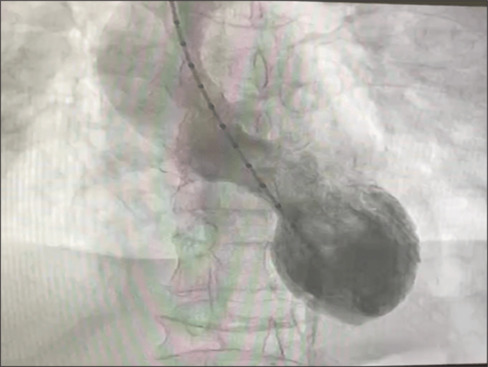

Takotsubo syndrome (TTS), also known as stress cardiomyopathy, is a life-threatening condition characterized by transient left ventricular dysfunction with nonischemic abnormalities. This syndrome in scenarios of anaphylactic shock is quite rare, with only a few cases reported. Early diagnosis and treatment are crucial. We presented a rare case of 58-year-old woman presented to our hospital due to an anaphylactic shock. The patient was stable and in the de-escalation dose of adrenaline (0.05 µg/kg/h). Twenty-two hours from exposure, the patient experienced pulmonary edema that required intubation, both adrenaline and dobutamine to maintain blood pressure. Echocardiography revealed a reduced ejection fraction of 35%. Subsequent coronary angiography showed no signs of coronary obstruction and left ventriculography provided typical apical ballooning and hyperkinesia in the basal region, highly suggesting TTS. The patient was successfully treated with inotrope and vasopressor and was discharged in stable condition after 7 days and improved normal heart function after 4 weeks. This case demonstrates the delayed onset of adrenaline-induced takotsubo complicated with pulmonary edema in a patient with anaphylactic shock due to antibiotics despite a de-escalation dose of adrenaline. Regardless of the duration of the event or the optimal epinephrine dosage in patients with anaphylactic shock, physicians should be aware of the risk of TTS.

Takotsubo综合征(TTS),也被称为应激性心肌病,是一种危及生命的疾病,其特征是短暂性左心室功能障碍伴非缺血性异常。在过敏性休克的情况下,这种综合征是相当罕见的,只有少数病例报道。早期诊断和治疗至关重要。我们提出一个罕见的病例58岁的妇女提出了我们的医院由于过敏性休克。患者病情稳定,肾上腺素降剂量(0.05µg/kg/h)。暴露22小时后,患者出现肺水肿,需要插管,肾上腺素和多巴酚丁胺来维持血压。超声心动图显示射血分数降低35%。随后的冠状动脉造影未见冠状动脉阻塞迹象,左心室造影显示典型的根尖球囊和基底区运动亢进,高度提示TTS。患者经肌力和血管加压药治疗成功,7天后出院,病情稳定,4周后心功能恢复正常。本病例显示了延迟发作的肾上腺素诱导的takotsubo并发肺水肿患者,尽管肾上腺素剂量降低,但抗生素引起的过敏性休克。无论过敏性休克患者的事件持续时间或最佳肾上腺素剂量如何,医生都应该意识到TTS的风险。